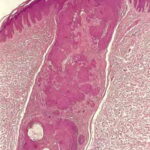

Inverted follicular keratosis = التقران الجرابي المقلوب